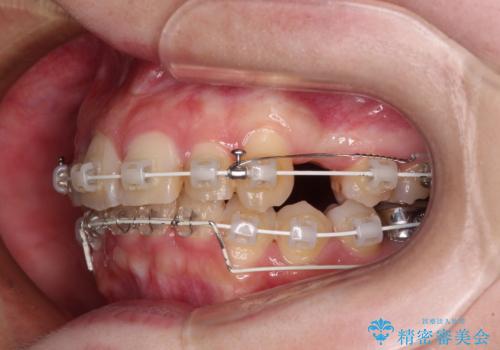

- 前歯のデコボコを気にして来院された患者様です。

上下の前歯にデコボコがあり、更にはディープバイトにより下顎前歯の大半が隠れている状態でした。

上顎左右第一小臼歯の2本を抜歯し、ワイヤー装置を使用して咬み合わせ高さを改善しながら、歯列を整えて行くこととしました。